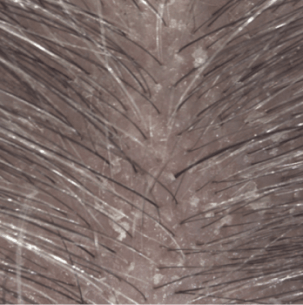

Keratolytic active ingredient inducing a significant loss of cohesion at the level of the stratum corneum: desquamation of thick patches on the scalp.

Efficacy results

Induration at 1 month (3).

(1) Clinical study on 54 subjects with light to moderate psoriasis on the scalp. 4 week attack phase: 3 shampoos per week

(3) Clinical assessment of plaque induration at D29.